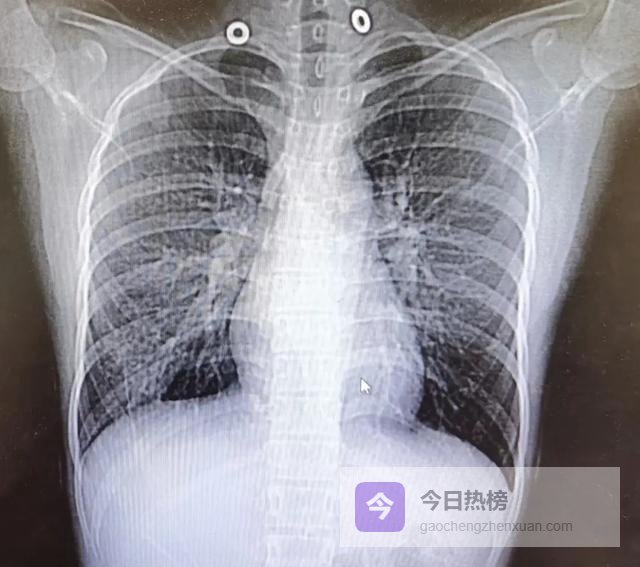

医生在评估肺癌风险时,并非简单地看有没有“结节”,而是聚焦于几个高度提示性的影像学特征。

当一份CT报告中完全未出现“磨玻璃密度”、“分叶征”、“毛刺征”、“胸膜凹陷”或“血管集束征”等描述时,临床普遍认为其恶性可能性极低。

“磨玻璃影”(Ground-GlassOpacity,GGO)之所以令人关注,是因为它往往代表肺泡壁增厚、细胞异常增生或早期腺癌原位阶段。

此时肿瘤细胞尚未完全取代肺泡结构,因此仍能透光,呈现出朦胧的“磨砂玻璃”样外观。若这种影子稳定存在超过3个月,尤其直径大于8毫米,医生会建议密切随访。

而“实性结节”本身并不可怕,多数是良性肉芽肿或陈旧瘢痕。真正让医生皱眉的是它的“长相”。一个边缘光滑、边界清晰的圆形小点,很可能是炎症愈合后的遗迹;

但若边缘呈“分叶状”——就像一颗不规则的土豆,表面凹凸起伏,这往往是肿瘤生长速度不均所致。

更值得警惕的是“毛刺征”,即结节周围放射出细短的线条,如同海胆的刺,这是肿瘤向周围组织浸润性生长的直接证据。

“胸膜凹陷征”描述的是结节牵拉邻近胸膜形成的小坑,仿佛用手指轻轻按压气球表面;“血管集束征”则指多条血管像被磁石吸引般汇聚向结节。

这两者都是肿瘤刺激局部纤维收缩和新生血管生成的结果。这些特征单独出现或许尚可观察,但若组合出现,恶性概率将显著上升。